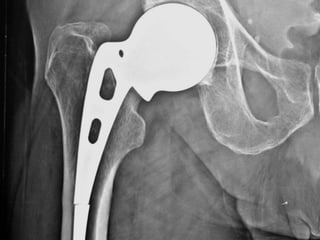

Observations

• All AMP were done in young age lasted long.

• Good quality bone support AMP well.

• Bone growth is noted in fenestrations of AMP.

• Hypertrophy of the calcar region noted in all

cases.

• There was no sign of loosening in any case.

• There was no sinking of proximal prosthesis in

femoral canal.

• Even in a well fixed prosthesis, there are

constant bending strain of cyclic loading

leading to remodeling of the proximal femur

and to varus setting of the head-neck of

prosthesis.

• A broken stem of AMP is a metal fatigue

failure.

• Since proximal part is well fixed, revision is not

required.

• The initial pain following breakage of stem is

due to change in the distribution of

mechanical forces, as the lateral femoral

cortex start bearing more load.